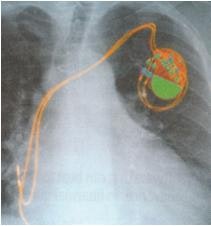

Some wind up radios and lights for Africa have no battery, the clockwork mechanism being carefully designed to provide constant torque that drives the device directly through a dynamo. Another imaginative form of electrodynamics is the experiment at Southampton University Hospital in the UK where two small, liquid filled balloons are inserted in the human heart and connected by a silicone tube containing a moveable magnet. As the heart beats, it squeezes each balloon in turn, pushing the liquid through the tube and taking the magnet back and forth with it. Because there is a coil embedded in the tube, this generates electricity to charge the battery in an embedded pacemaker or defibrillator. The hope is that the system could be left in for the life of the patient or at least greatly reduce the need for intrusive surgery, even providing enough power to radio diagnostic and performance data. Faraday would have been proud. In a heart conference in late 2008, developer Paul Roberts said that the power taken does not significantly burden the heart. The output of 4.3 microjoules per heart beat is expected to double with use of better polymers.

Source: University of Southampton Hospital